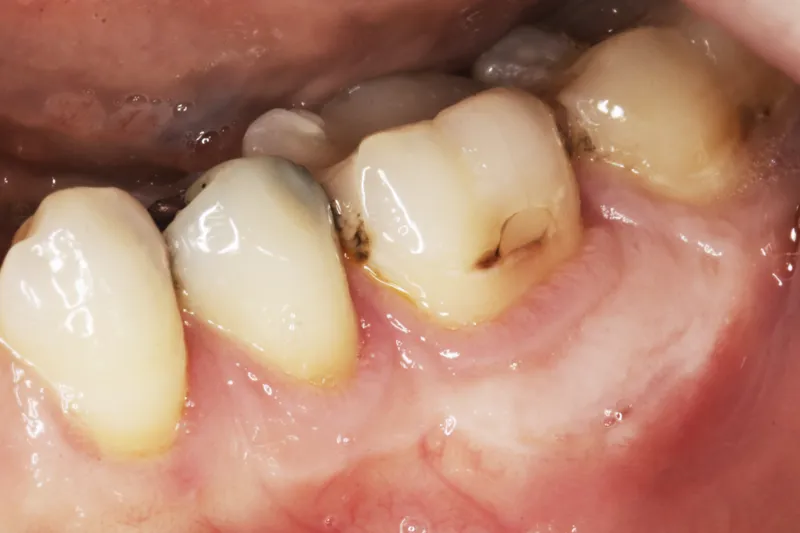

Patienttilfælde– En 28-årig kvinde blev henvist til Kæbekirurgisk Afdeling, Sydvestjysk Sygehus Esbjerg, Syddansk Universitetshospital, for fjernelse af slimhindeforandring på gingiva. Der blev foretaget en incisionsbiopsi, og forandringen var histologisk forenelig med oral fokal mucinose. Excision af hele forandringen og simultan rekonstruktion med frit transplantat af ganeslimhinde blev foretaget. Fornyet histologisk undersøgelse viste mod forventning et perifert odontogent myksom. Ved kontrol tre år efter excision af forandringen fandtes sunde forhold og ingen tegn på recidiv.

Case study – A 28-year-old female was referred to the Department of Oral and Maxillofacial Surgery, University Hospital of Southern Denmark, Esbjerg, for removal of a mucosal lesion on gingiva. An incision biopsy was made, and histological examination revealed oral focal mucinosis. Excision of the lesion was performed, together with reconstruction with a free palatal mucosal graft. Histological examination revealed peripheral odontogenic myxoma. 3-years follow-up showed no sign of recurrence.